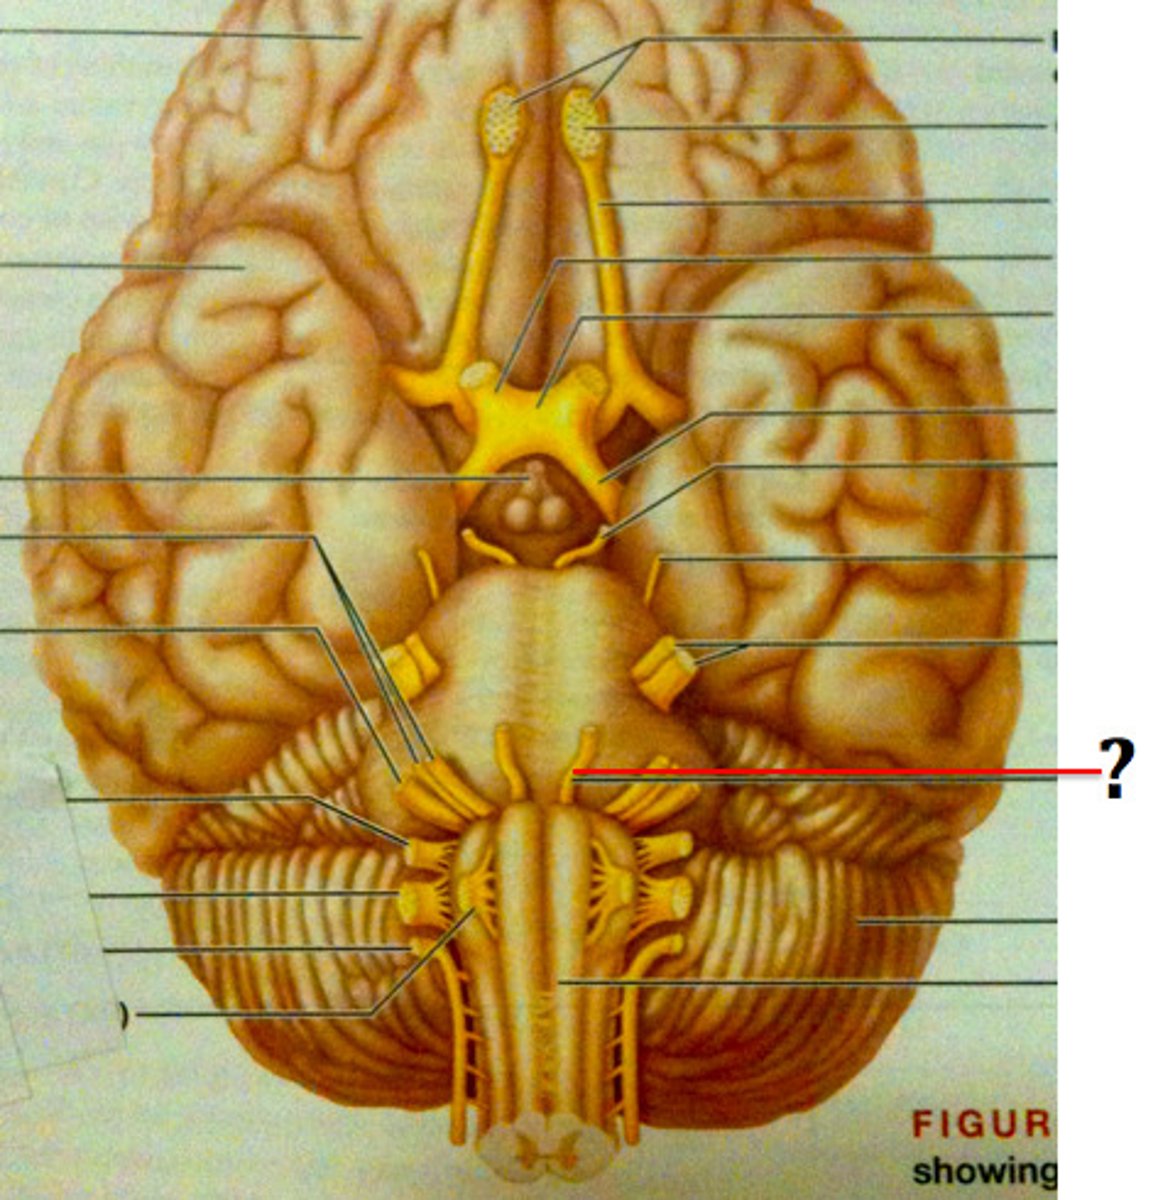

olfactory bulb

olfactory nerve

optic nerve

Oculomotor Nerve (III) - narrows pupil and focuses lens

Trochlear Nerve (IV) - eye movement

Trigemminal Nerve

Abducens Nerve (VI) - lateral eye movement

Facial Nerve (VII) - Movement of facial expression muscles, taste (from anterior 2/3 of tongue)

Vestibulocochlear (VIII) - Equilibrium and Hearing (Special Somatic Sensory)

glossopharyngeal nerve (IX)

vagus nerve

Hypoglossal Nerve (XII) - Controls muscles of tongue

Accessory nerve (XI) - controls trapezius & sternocleidomastoid